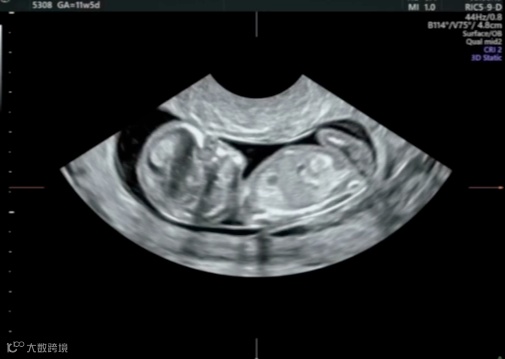

达叔在公众号文章《为何需要选择正确的胎儿生长参数》录制了如何设置超声机器的胎儿生长参数,这次达叔录制了一个应用容积数据后处理的方法,解决无法通过常规扫查完成的NT测量

大家在看完视频后,最大的疑问可能是:容积数据测量NT靠谱吗?这个问题,其实已经有大量的研究论证过。目前的研究表明:在良好的容积数据中获取的NT、头臀长等数据,与二维超声获取的数据,没有统计学差异。

在经腹部检查时,有时受胎儿体位、子宫位置、腹壁脂肪等多种因素影响,难以获得理想的切面,这个时候就可以考虑经阴道超声来测量NT。

但是,超声探头在阴道内活动度有限,要获取理想的切面,对胎儿位置要求很高,而很显然,这是我们无法控制的。经阴道超声测量NT有一些小技巧,比如调整容积探头的β-view角度可以获得更理想的切面,但总的来讲,这些技巧对操作熟练度要求仍然很高。

但阴道探头频率高分辨率高,获得的容积数据也同样具有更多的细节,这使得利用容积数据获取标准切面成为可能。这个视频就教大家如何处理容积图像。

先在这个切面上获取容积数据,这里有一个小细节,胎儿任何的活动都可能使容积数据分辨率大大下降,所以一方面采集图像要在胎儿静息时,另一方面可以嘱咐孕妇在图像采集时屏住呼吸。